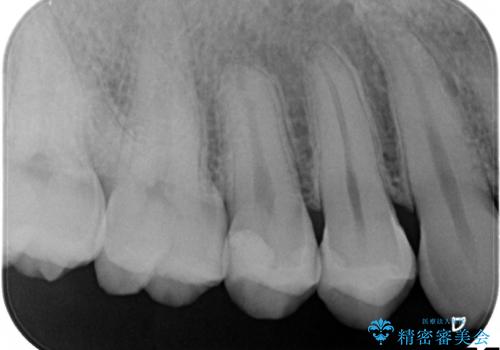

- 時々冷たいものがしみるといらした患者様です。

歯科医院に行くこと自体が久しぶりだったようで、口腔内にはたくさん虫歯がありました。

小さな虫歯に関しては保険内の白い詰め物にて、虫歯の大きい箇所はセラミックインレーにて修復しました。